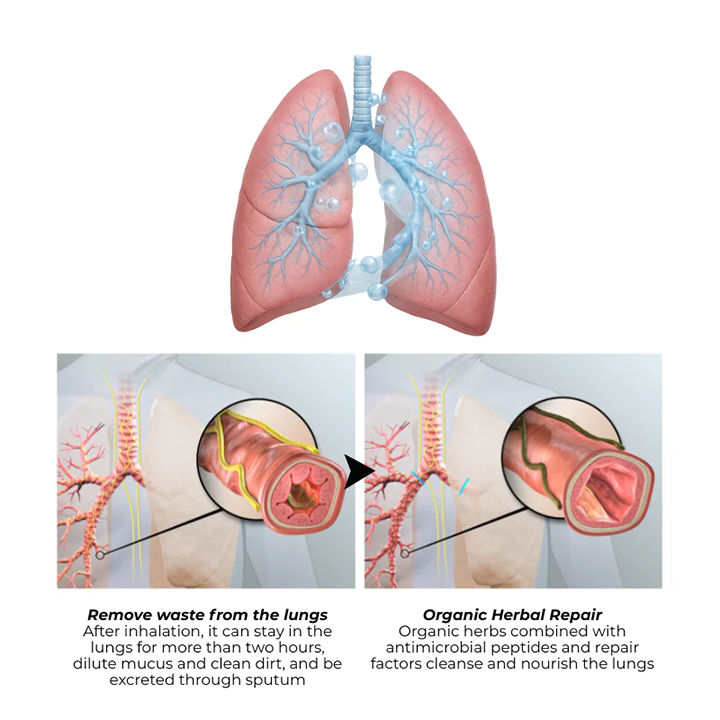

🌿Dual Effect: Relieves Breathing Discomfort and Promotes Smooth Breathing

🌿Dual Effect: Relieves Breathing Discomfort and Promotes Smooth Breathing

Breathe Qooes™ Mullein Aroma Diffuser’s refreshing air helps promote smoother breathing, providing a comfortable and fresh environment.

This diffuser has soothing properties that purify the air, allowing you to breathe more easily while promoting a sense of calm and relaxation. It also enhances oral freshness, leaving your breath feeling clean and revitalized.

Lung Detoxification and Enhanced Oral Freshness

The Breathe Qooes™ Mullein Diffuser helps detoxify your lungs and improve your breathing experience. It also freshens your mouth air for cleaner, healthier breath with every use.

Traditional oral supplements deliver only 20-40% of active compounds to your lungs after passing through your digestive system. Qooes® Breatheora's nasal inhalation technology delivers 90-100% bioavailability directly to your respiratory system within 2 minutes.

Scientific studies confirm nasal delivery achieves 2-4 times higher effectiveness than oral capsules, drops, or patches. While oral supplements take 45-90 minutes to reach peak effect, nasal inhalation works within 2 minutes.

When you need respiratory relief, every second counts. That's why customers experience such dramatic differences with nasal inhalation - you're getting maximum potency exactly where you need it, exactly when you need it.

💨 Relieve Respiratory Discomfort – The New Upgrade Mullein Aroma Diffuser helps clear the airways and soothe breathing.